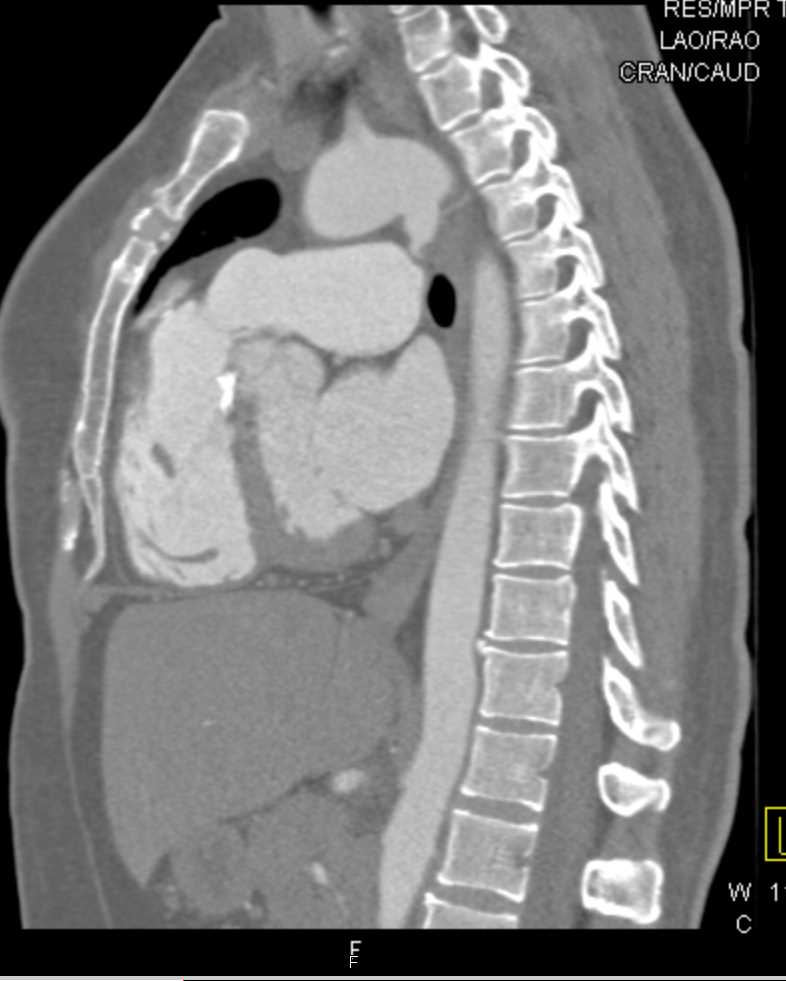

Ductus Aneurysm